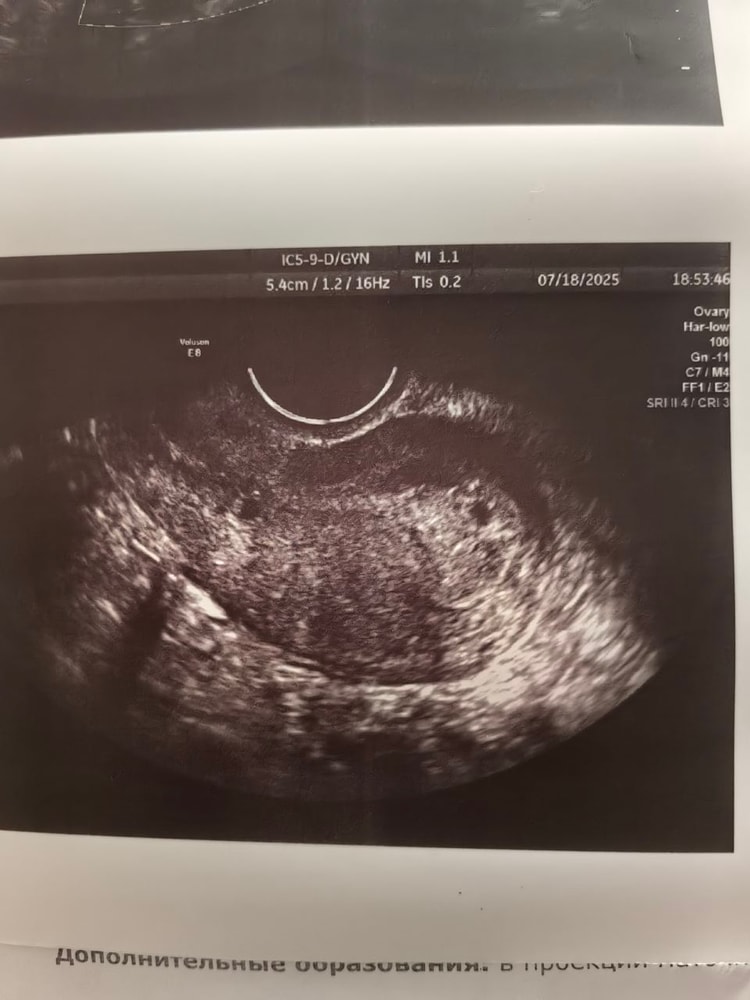

Марина, и я вот не верю, да и не хочется верить🙏 Мне ещё узи когда сделали впервые, я вышла и на снимке 2 "пятнышка" чёрных увидела, я уже подумала что двойня. У гинеколога спросила, она в ступор встала, потом говорит что не может там плодное яйцо крепиться, там шейка матки мол идёт. А по снимку я изначально подумала что это и есть плодное яйцо, там если присмотреться, будто бы видно шарик - жёлтое тельце. Загадочная ситуация, либо это я уже с ума схожу

Марина, Изображение Изображение